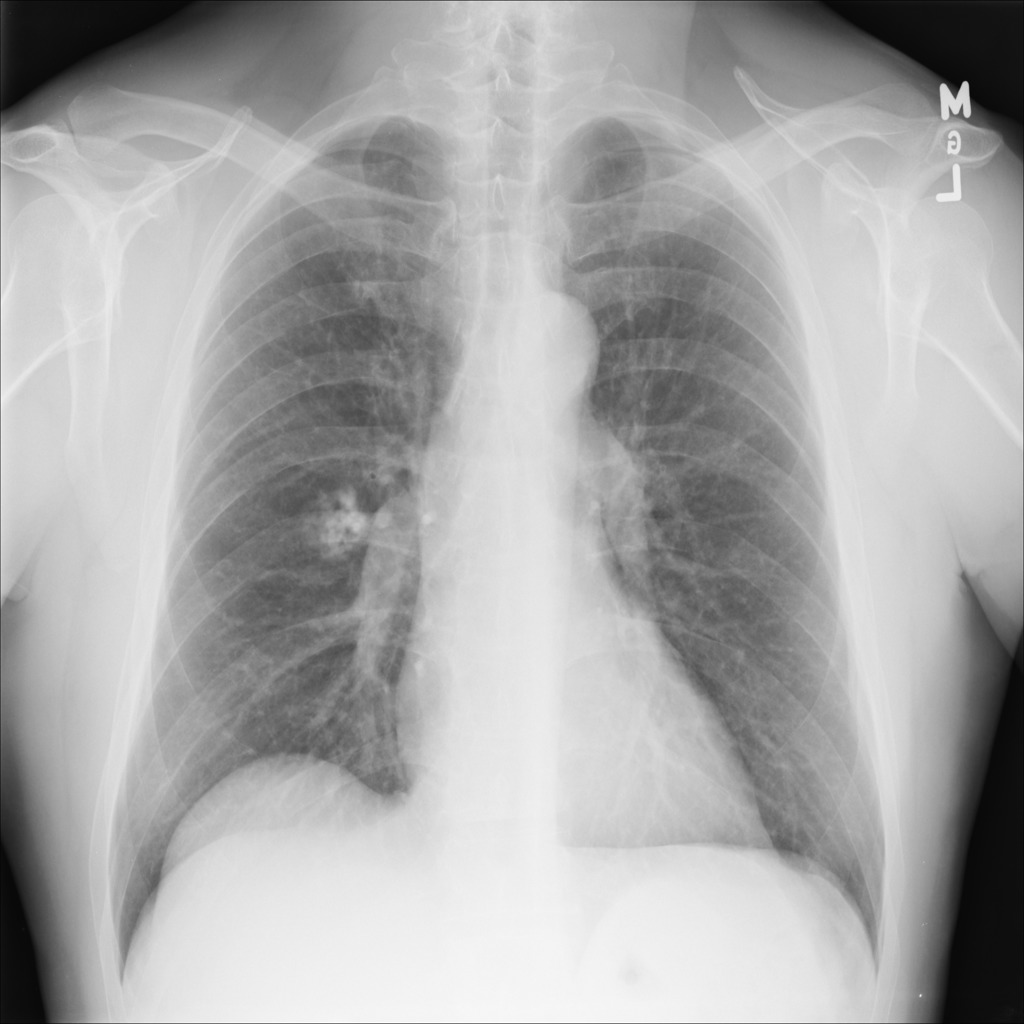

Examples of abnormal images generated by the proposed simulator are shown in the Figure 4.

Figure 4: Examples of abnormal images generated by the proposed simulator. The left is a normal lung image, and the middle is the abnormal image generated by the simulator. In the right, the location where the lesion has been inserted in the middle image is visualized by the blue bounding box.